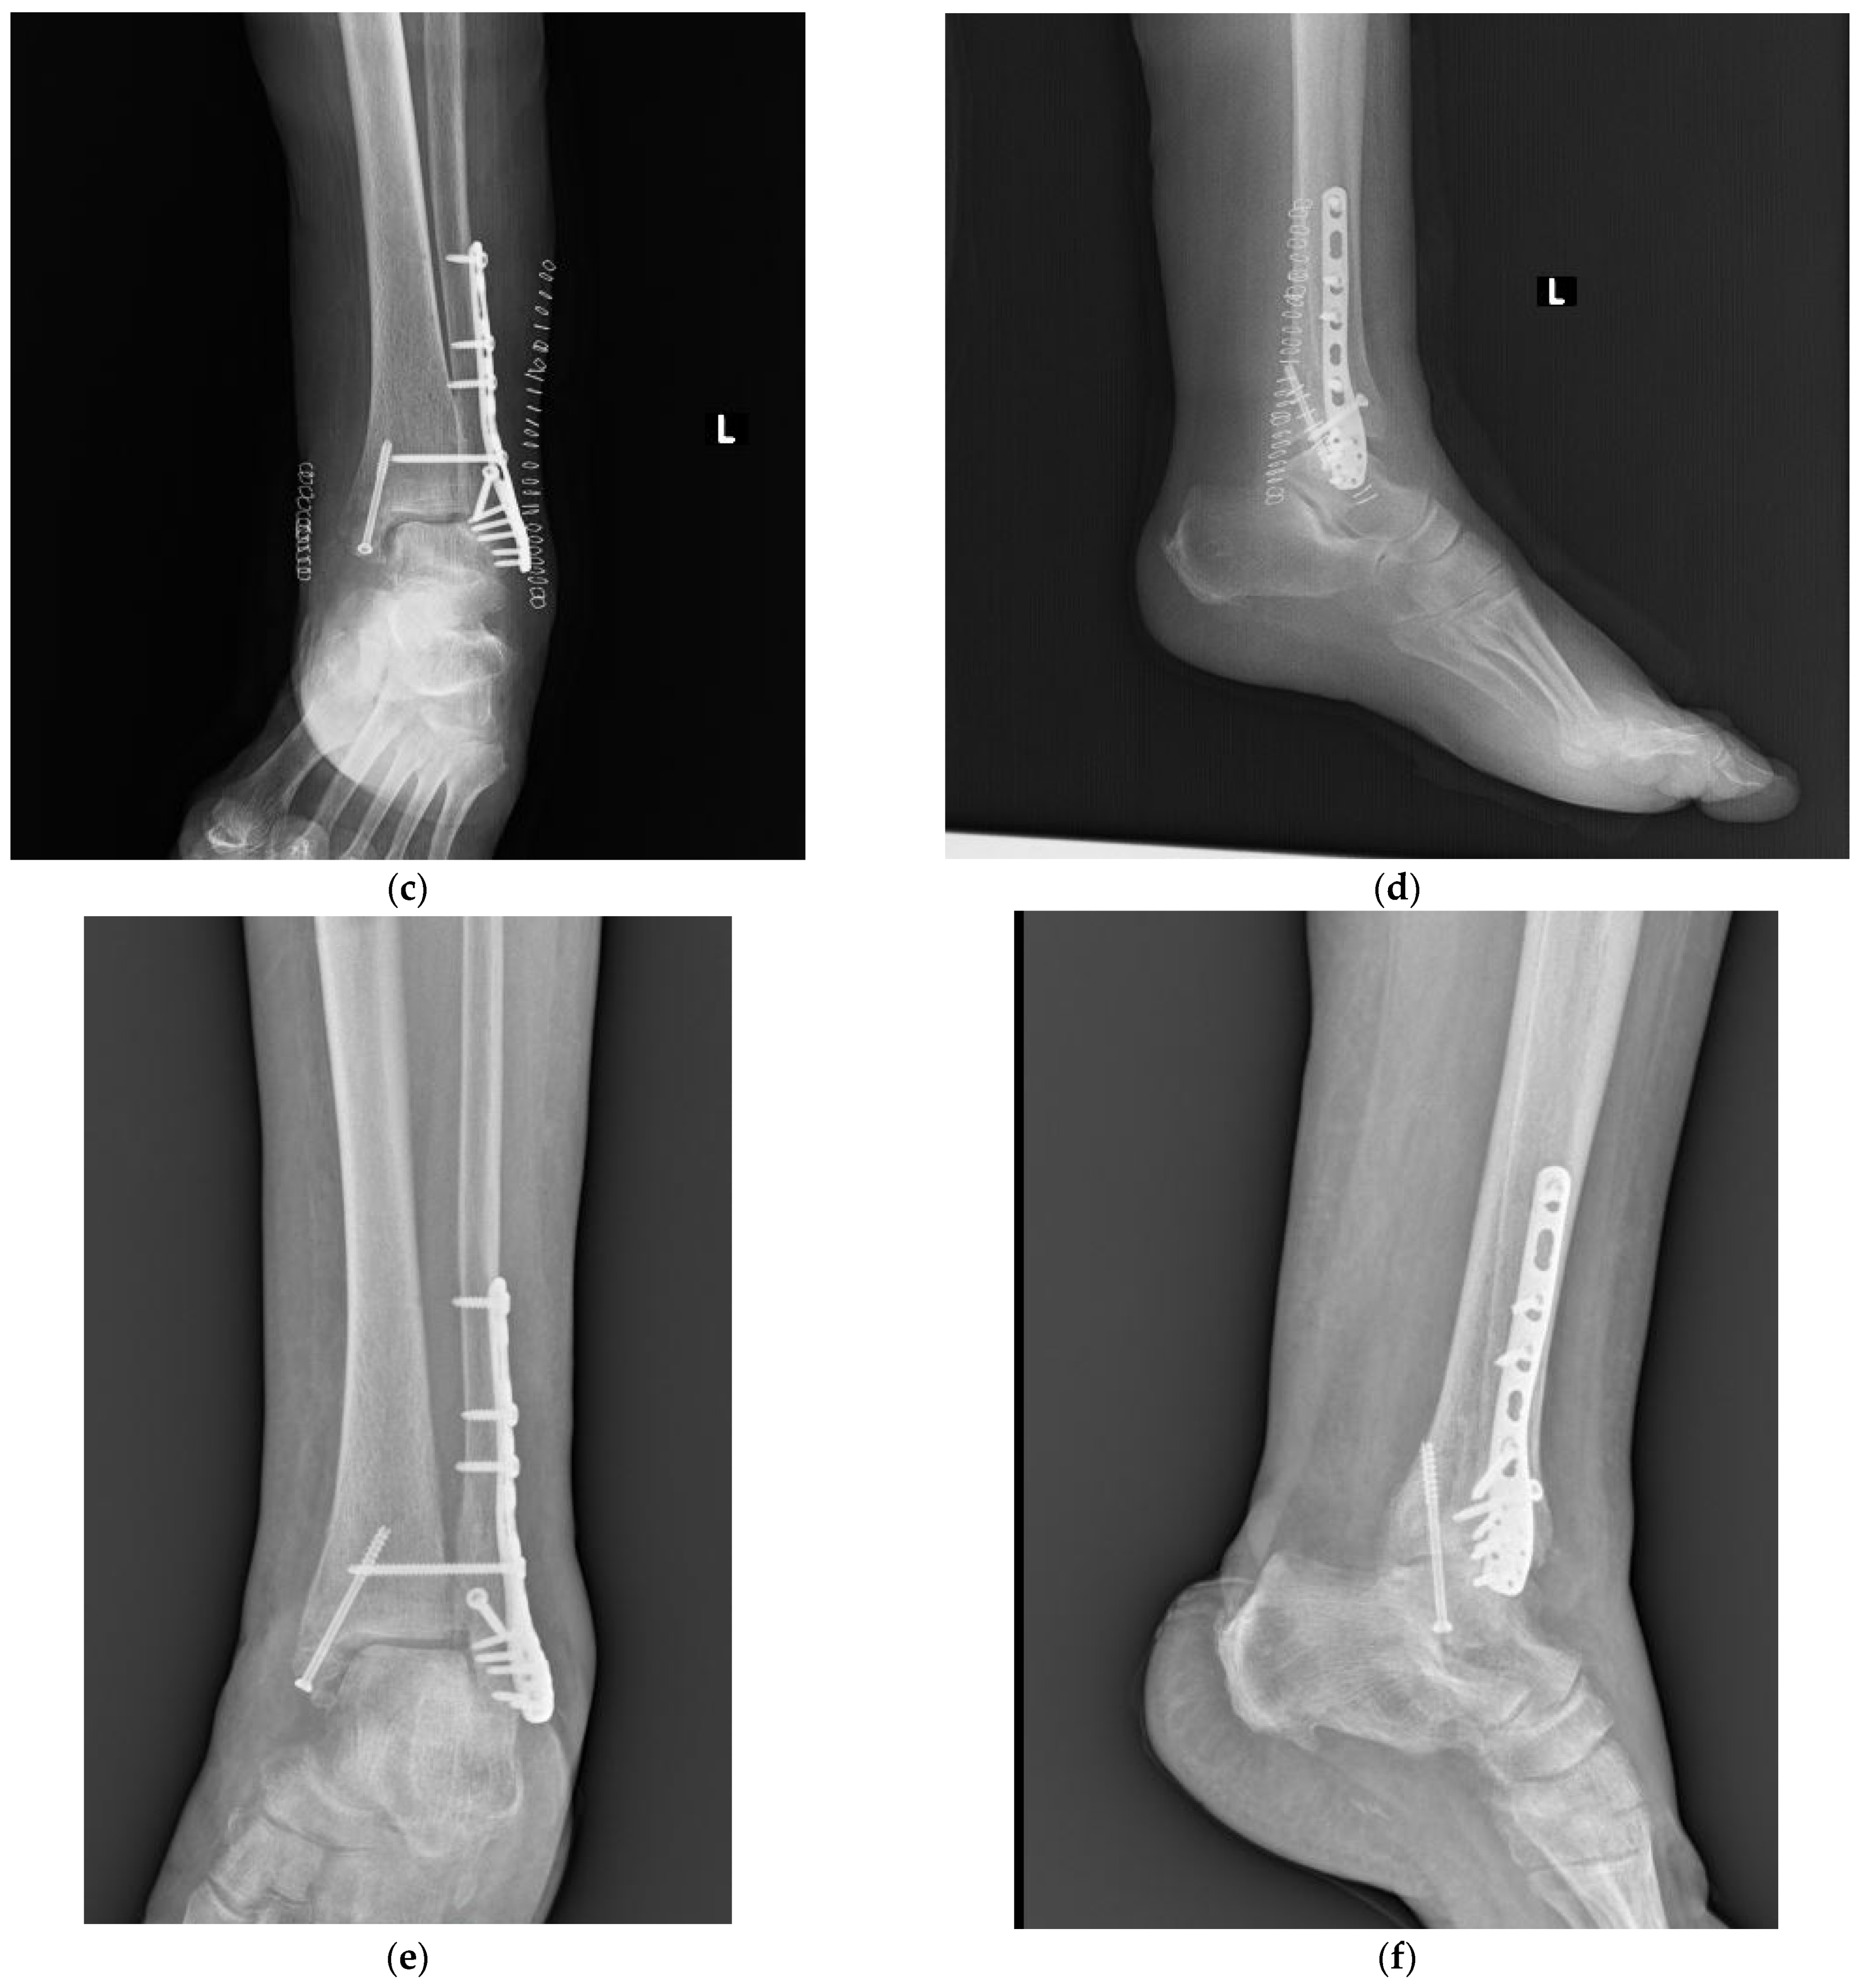

In 1947, David M. Bosworth [1] reported five cases of particular fracture-dislocation of the ankle, in which the proximal fragment of the fibula was incarcerated behind the posterior tibial tubercle. Since that time, this rare ankle fracture pattern has been called “Bosworth fracture” (an example is shown in Figure 2).

Figure 2.

X-ray of a Bosworth fracture (a) anterio–posterior (AP) pre-operative view, (b) lateral pre-operative view, (c,d) post-operative X-rays, and (e,f) the 4-month follow-up.